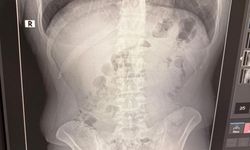

Kazada hafif yaralanan kaymakam Eskimez, Ulaş İlçe Hastanesi'nde yapılan ilk müdahalenin ardından, Sivas Numune Hastanesi'ne sevk edilerek tedavi altına alındı.